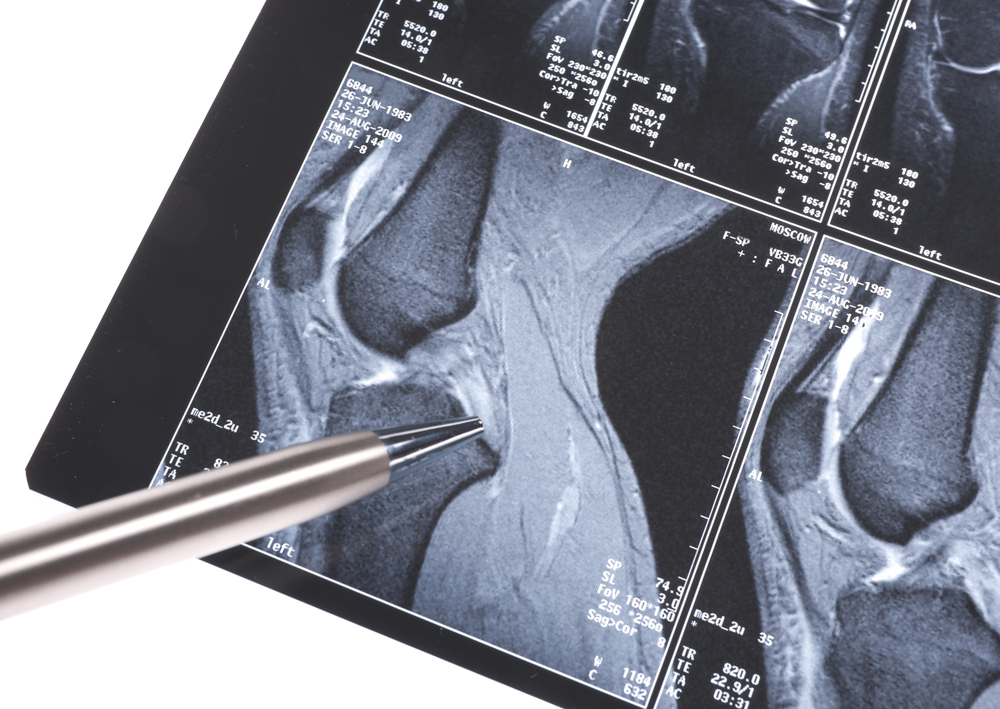

La artroscopia de rodilla es un procedimiento quirúrgico mediante el cual se introduce una cámara muy pequeña en la rodilla del paciente para visualizar la articulación. La cirugía de artroscopia de rodilla sirve para diagnosticar y tratar algunos problemas de la rodilla.

La artroscopia de rodilla se utiliza para diagnosticar y tatar los siguientes problemas:

Menisco roto

Lesiones de ligamento cruzado anterior o ligamento cruzado posterior

Lesión de ligamento colateral

Inflamación de la membrana sinovial (revestimiento de la articulación).

Rótula fuera de su posición

Pedazos pequeños de cartílago roto en la articulación.

Reparación de defectos en el cartílago

Algunas fracturas de huesos de la rodilla